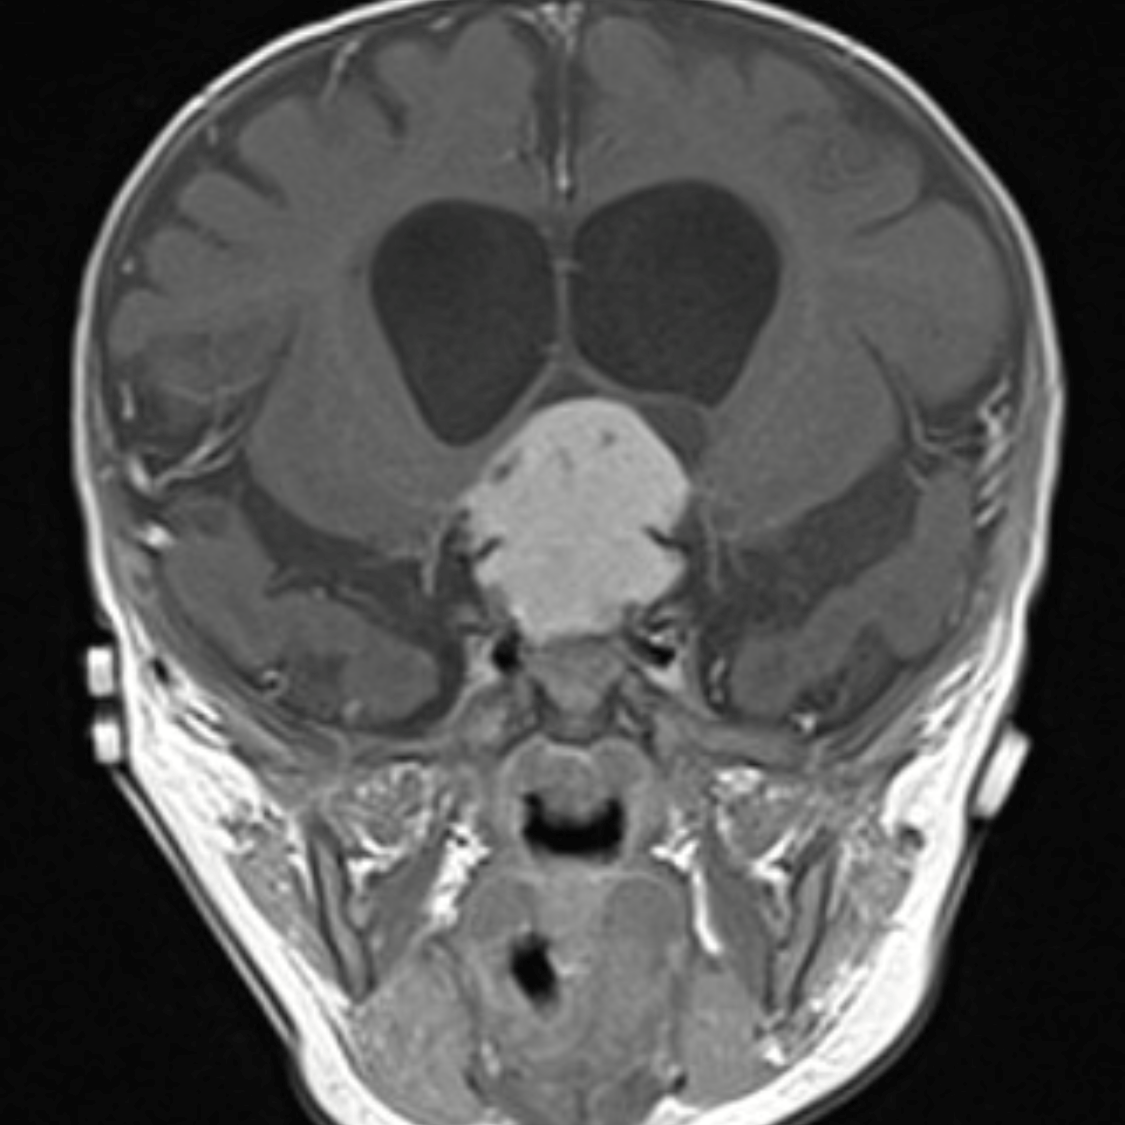

Last year, the World Health Organization reclassified brain tumors with a strong emphasis on differences at the molecular level. JHM neurosurgeon Alan Cohen, M.D., published an article about how these approaches can offer targeted therapy to improve outcomes and reduce treatment complications.